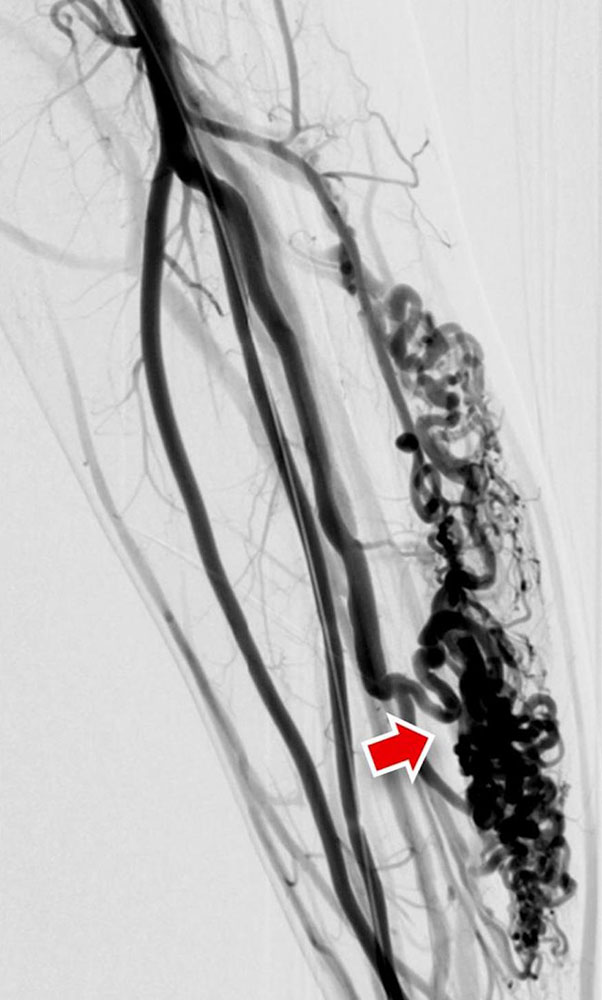

Fast-flow malformation (AVM and AVF): The exact anatomical morphology and the hemodynamics of a fast-flow vascular malformation can be very accurately analyzed with the use of DSA. The most important feature of a fast-flow vascular malformation is the immediate contrast filling of the draining veins via the nidus. Angiographically, fast-flow malformations can be categorized into four subtypes:

• In type I, there are up to 3 direct arteriovenous connections (AV fistulas) without an identifiable nidus

• In type II there is a dominant drainage vein, this can be aneurysmal.

In advanced disease, the incoming and outgoing vessels are also increasingly tortuous and dilated. In some cases, flow-related aneurysms are formed.